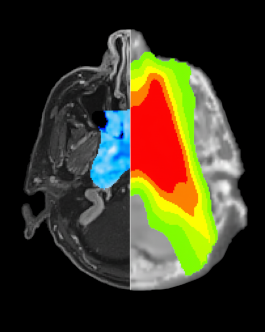

Les membres du laboratoire élisent chaque année la plus belle image créée au sein du laboratoire au cours de l'année écoulée. L'image 2025 lauréate est issue de travaux menés en oncologie pour la plannification du traitement. La partie à gauche correspond à une image par résonance magnétique pondérée T1 après injection de gadolinium, avec superposition de la carte de la composante de diffusion pure. La partie de droite représente une tomodensitométrie synthétique dérivée de l’imagerie par résonance magnétique, avec superposition de la distribution des isodoses pour la radiothérapie, représentée par un code couleur.